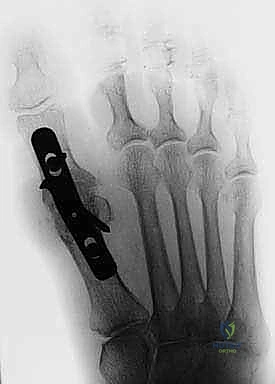

Illustration of arthrodesis of the first - Dr. Mohammed Hutaif

Internal Fixation

Once the optimal position is achieved, provisional fixation is obtained with smooth Kirschner wires. Multiple fixation constructs are biomechanically sound and clinically utilized.

The most common contemporary construct is a low-profile dorsal titanium plate combined with an independent interfragmentary lag screw. The lag screw is typically placed from the medial aspect of the metatarsal head, directing distally and laterally into the proximal phalanx, providing robust compression across the arthrodesis site. Following lag screw insertion, a pre-contoured dorsal plate is applied. Locking screws are placed into the metatarsal and phalanx to provide a neutralization construct that resists bending and torsional forces.

Alternative methods include crossed interfragmentary lag screws (which require excellent bone stock and precise technique), or intramedullary memory-metal staples.

Final Fixation Construct

Figure: Final fixation construct demonstrating compression and stability.

Fluoroscopy Final AP

Figure: Final intraoperative AP fluoroscopic image.